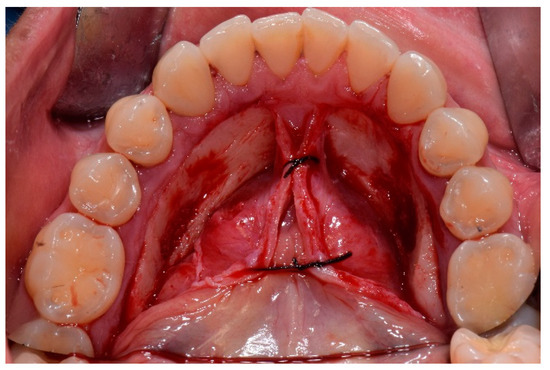

3. Treatment